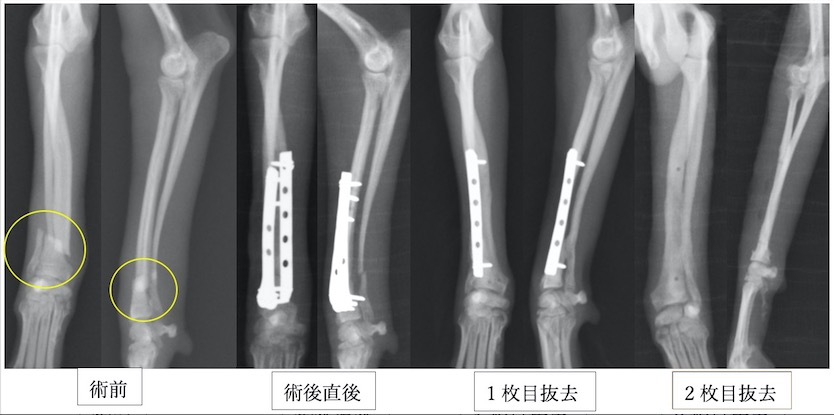

トイプードル9歳の橈尺骨骨折です。1.5mmスクリューを使用しています。

トイプードル2歳の橈尺骨骨折です。1.5mmスクリューを使用しています。

上の3症例ともにやや中央寄りの先端部の橈尺骨の横骨折(遠位骨幹部橈尺骨横骨折)です。直線のプレートを使用しています。

ポメラニアン半年齢の橈骨尺骨骨折です。1.3mmの超小型スクリューを使用しました。

上の4症例はやや中央寄りの先端部の橈尺骨の横骨折(遠位骨幹部橈尺骨横骨折)です。直線のプレートを使用しています。